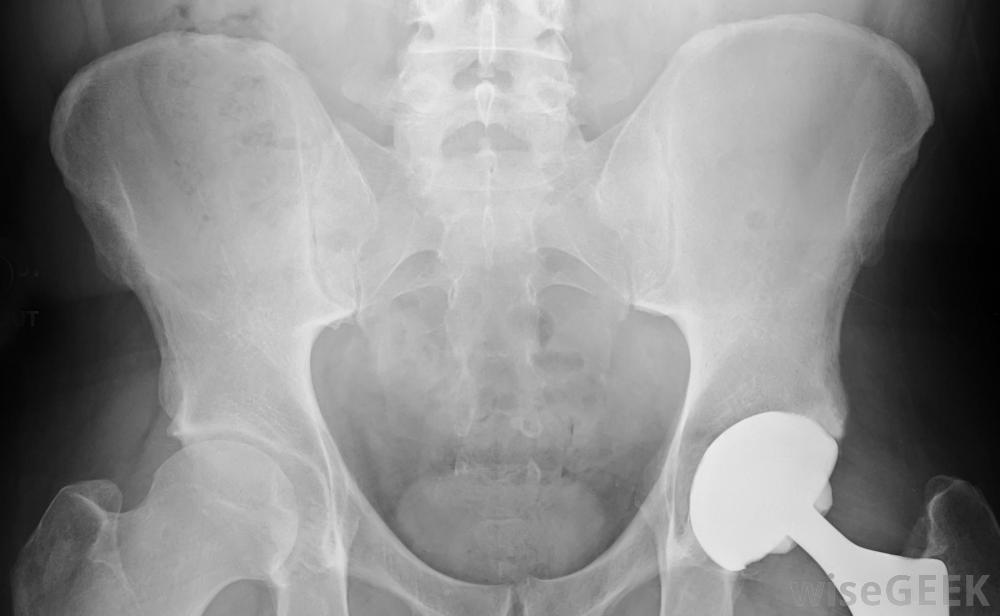

人造髋关节是一种假肢装置。